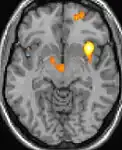

Positron emission tomography (PET) scans indicate the brain areas which are activated during attack only, compared to pain free periods. These pictures show brain areas that are active during pain in yellow/orange color (called "pain matrix"). The area in the center (in all three views) is specifically activated during CH only. The bottom row voxel-based morphometry (VBM) shows structural brain differences between individuals with and without CH; only a portion of the hypothalamus is different.[33]